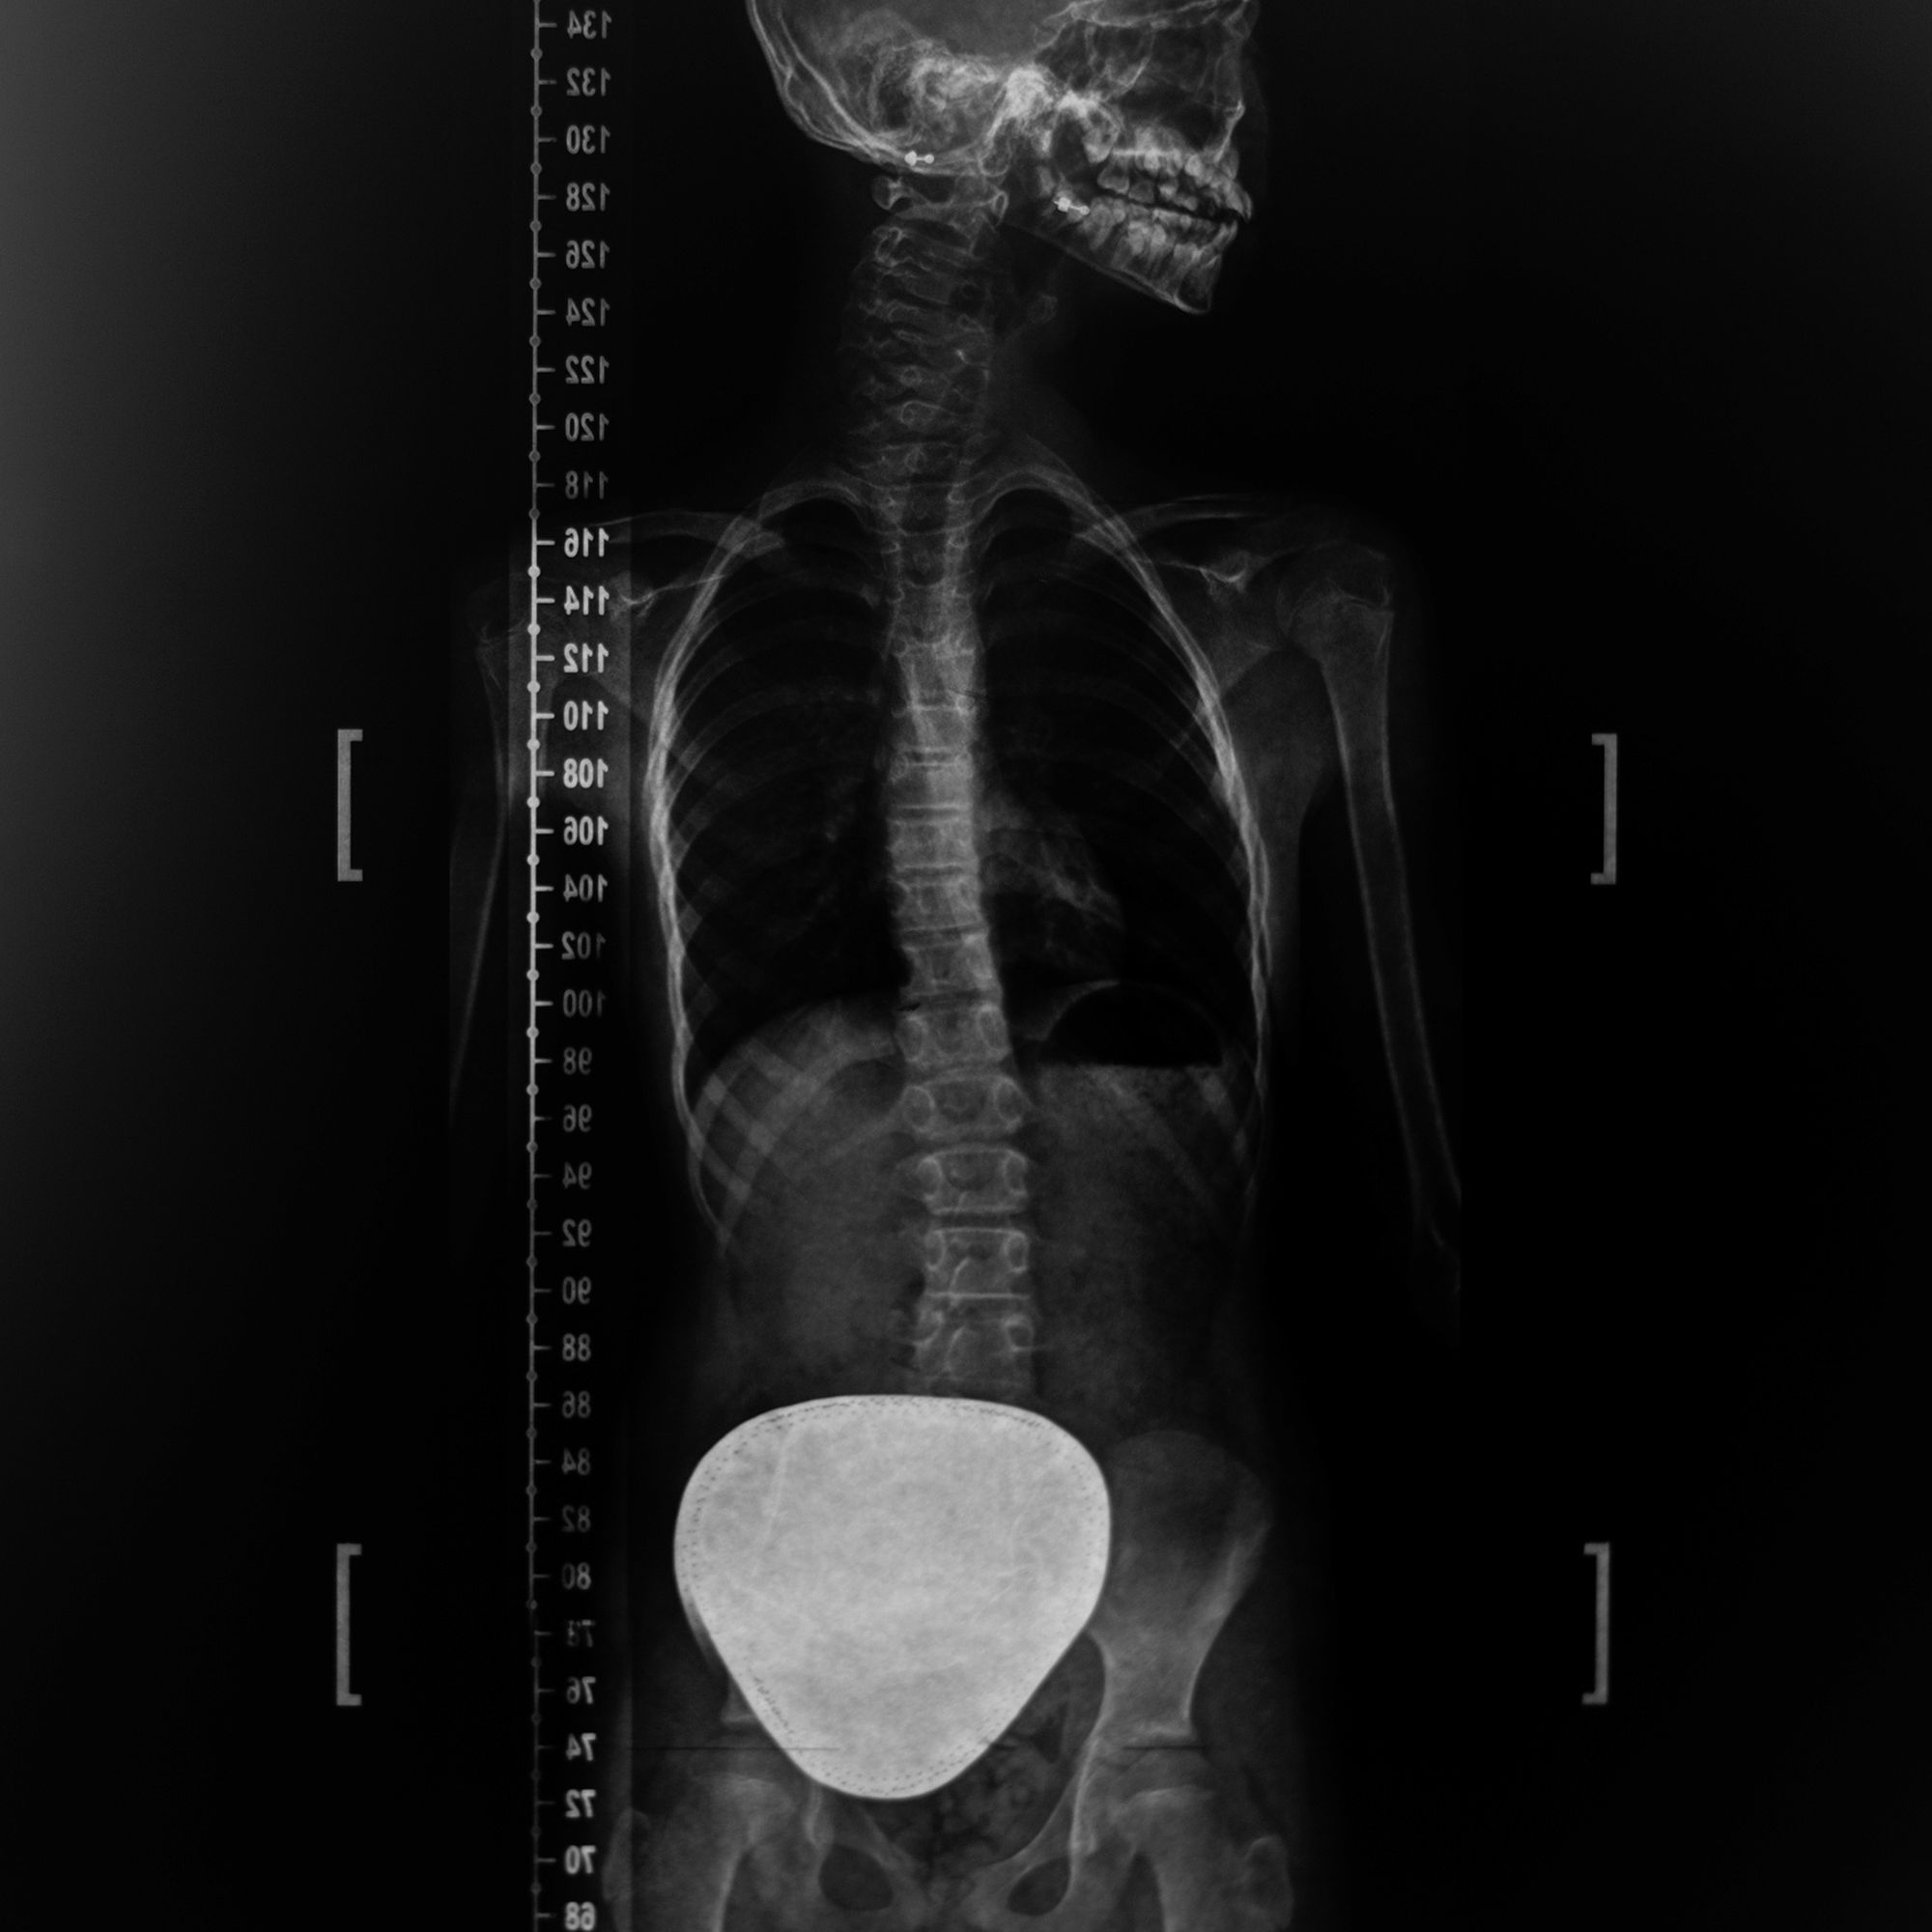

Scoliosis